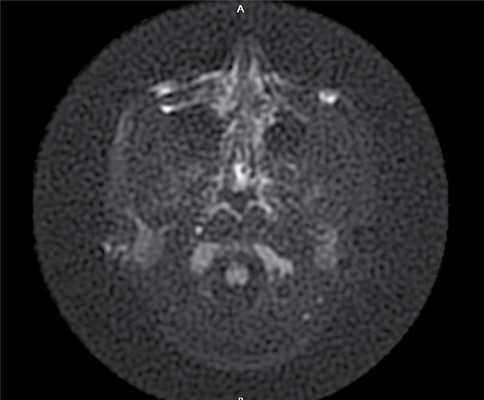

Через 6 мес по результатам отомикроскопии, МСКТ височных костей, МРТ среднего уха в DWI-режиме: в сосцевидном отростке, в аттико-антральной области, в области нижней и задней граней пирамиды височной кости визуализируется обширная послеоперационная полость; в барабанном и мастоидальном сегментах послеоперационной полости пристеночно визуализируется содержимое умеренно неоднородной структуры, гетерогенного МР-сигнала в Т2 ВИ, STIR, T2 flair, изоинтенсивное в Т1 ВИ, без повышения сигнала на DWI c коэффициентом В 1000 и вычитанием на ИКД-картах (вероятно, рубцово-фиброзные изменения): данных за рецидив холестеатомы получено не было (рис. 4). Рис. 4. МР-томограмма среднего уха, выполненная в DWI- режиме.